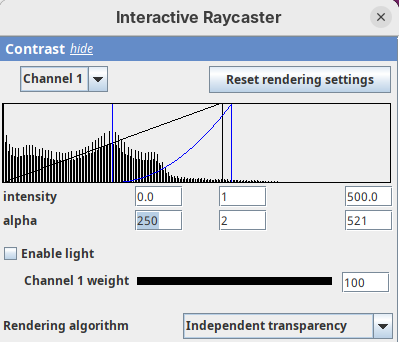

Contrast

The Contrast section shows a histogram of pixel intensities of the image for each channel, which we can choose using the dropdown menu. We can set the minimum, gamma, and maximum values for the intensity and alpha (transparency) properties of each pixel. The weight option controls the general opacity of the channel (0=invisible, 100=visible). There’s also more advanced options like lighting and rendering algorithm which we’ll simply use the default states as they are usually good for most use cases.

Adjusting the intensity and alpha values is the most impactful way to improve the 3D rendering. With the intensity setting we can define which pixel value in the image corresponds to total black (minimum) and which corresponds to total white. It’s the same as in the standard Brightness & Contrast tool. By default, 3Dscript will load these values from the original stack. In this case, it loaded min=3 and max=521.

Let’s change these values to see how it impacts the 3D rendering.

- Change the intensity minimum to

250.

You will see that the darkest parts of the rendering will become even darker and no longer visible. We are losing real information from the data; we do not want that.

- Set the

minto0, for now. - Then, change the

maxto250.

The brightest parts of the rendering will become all white. It is so bright that we can no longer resolve details of the surface. We are losing information and also do not want that.

- Set the

maxto500.

Note that when you change an intensity value, the min/max black line in the histogram moves. You can also grab the line and move it manually to change the values.

The blue line represents the alpha values. In 3D rendering, a pixel has a transparency value linked to its intensity. The alpha min defines the value for full transparency and the max the value for full opacity.

- Set the alpha

minto250.

This will make darker pixels more transparent and information gets lost.

- Set it to

0.

By default 3Dscript sets the gamma value of alpha to 2.0. That’s a good default for fluorescence microscopy (see the next dataset below), but since this is MRI data, we need to tweak it a little differently.

- Set the alpha gamma value to

1.0.

Note that this improves the visualization as the head’s surface becomes better visible.

- Now set the alpha

maxto250.

The surface will become even more solid because we are defining that pixels that have a value above 250 will be fully opaque.

- To compare, set alpha

maxto5000.

You will notice that the sample will become more transparent. Even the brain inside the skull will be visible.

- Set alpha

maxback to500.

Generally, setting the intensity and alpha to the same values is a good starting point for optimizing the rendering.